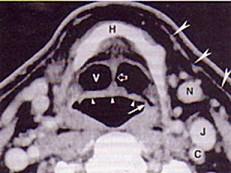

男,55岁,声嘶6年,有长期吸烟史。检查:无呼吸困难。喉镜检查:声带慢性充血,可见右侧声带可见菜花样新生物,右侧声带活动固定,喉部CT检查如下图:诊断...

问题 男,55岁,声嘶6年,有长期吸烟史。检查:无呼吸困难。喉镜检查:声带慢性充血,可见右侧声带可见菜花样新生物,右侧声带活动固定,喉部CT检查如下图: 诊断首先考虑 ( )